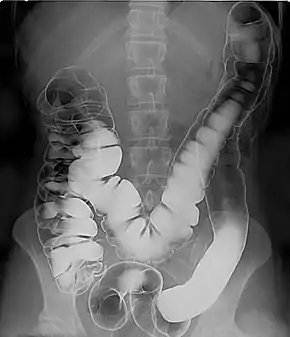

Air

- Barium enema (large bowel investigation) and DCBE (double contrast barium enema).